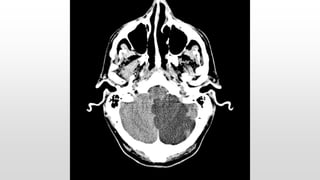

This document discusses various cases of collapse and syncope. It defines collapse as transient loss of consciousness with loss of postural tone and full recovery. Syncope is defined as loss of postural tone with or without loss of consciousness and full recovery. It then discusses the multiple potential causes of collapse and syncope including toxicological, cardiac conduction abnormalities, structural cardiac issues, autonomic dysfunction and more. It then goes through 9 case examples, discussing important questions to ask, potential tests and interventions for each case.